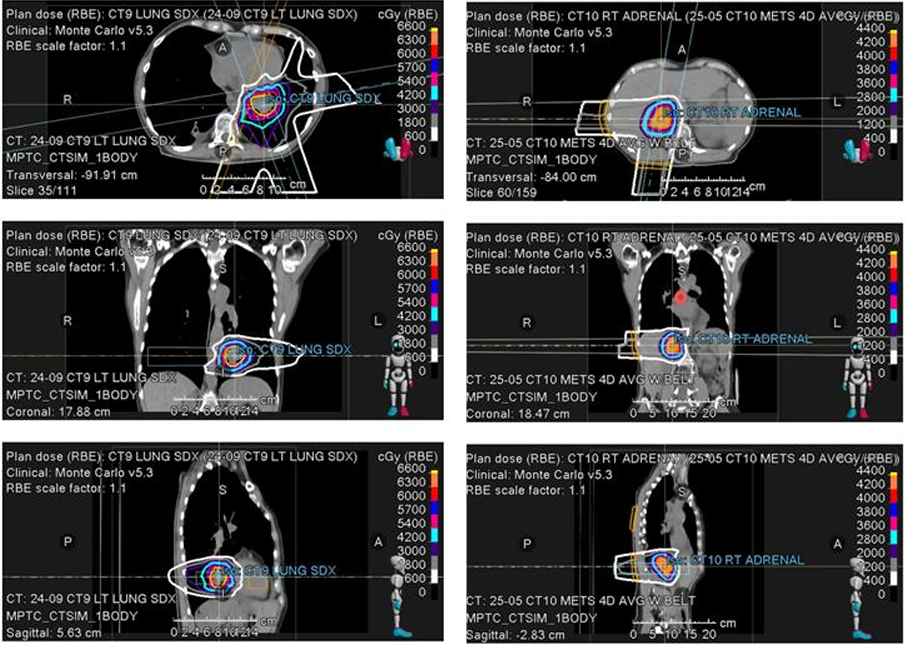

2021年5月,患者因右肺上叶主结节出现孤立性进展,接受立体定向放射治疗(SBRT),剂量为55Gy,分10次照射。治疗后,无进展生存期(PFS)达12个月,展示局部巩固治疗在控制寡进展中的有效性。然而,2022年6月,患者在维持免疫治疗期间,右肺下叶和左肺下叶出现新病灶,接受SBRT治疗,剂量分别为62.5Gy(分10次)和50Gy(分5次,每次10Gy,隔日一次)。同年7月,患者出现左额叶脑转移,经手术切除后,接受SBRT至切除腔,剂量为27Gy(分3次),每次9Gy。这表明,对于寡转移病灶,局部巩固治疗能够有效延长患者的PFS。

8e2cb4a1-c3f2-4c9c-b580-39f41bac524f.png

2e89fc77-9071-479e-aafb-851099f8b5ee.png

2023年9月,患者开始使用Adagrasib,针对KRAS G12C突变。然而,PFS仅为11个月,左下肺叶结节出现进展。团队采用质子治疗,剂量为60Gy,分12次照射。2024年6月,患者纵隔淋巴结和右肾上腺出现寡进展,再次接受质子治疗,剂量分别为45Gy(分15次)和40Gy(分5次)。这表明,精准医疗在控制寡进展病灶方面具有显著优势,但其疗效可能受肿瘤生物学特性等多种因素影响。